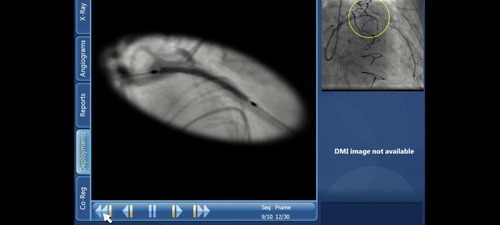

Use of SyncVision to ensure accurate positioning of the stent

SyncVision was used by the live case operators to ensure that the stent was positioned in the pre-defined location.

• SyncVision to Co-register IVUS and angiographic images

• SyncVision automated Stent Enchancement